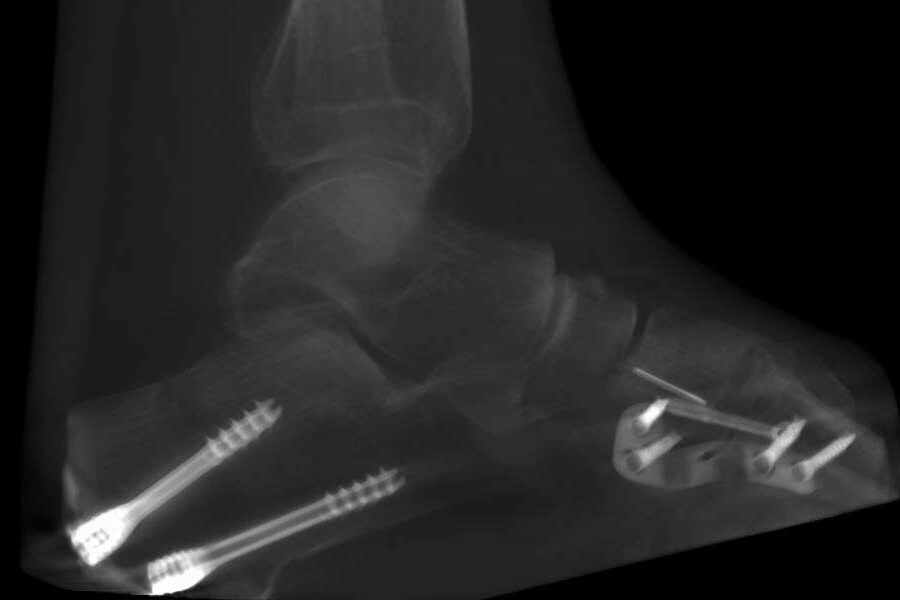

Home Schwerpunkte Krankheitsbilder Schwerer Knick-Plattfuß (Knick-Senkfuß) complex flat foot surgery case by Dr. Stefan Böhr

complex flat foot surgery case by Dr. Stefan Böhr